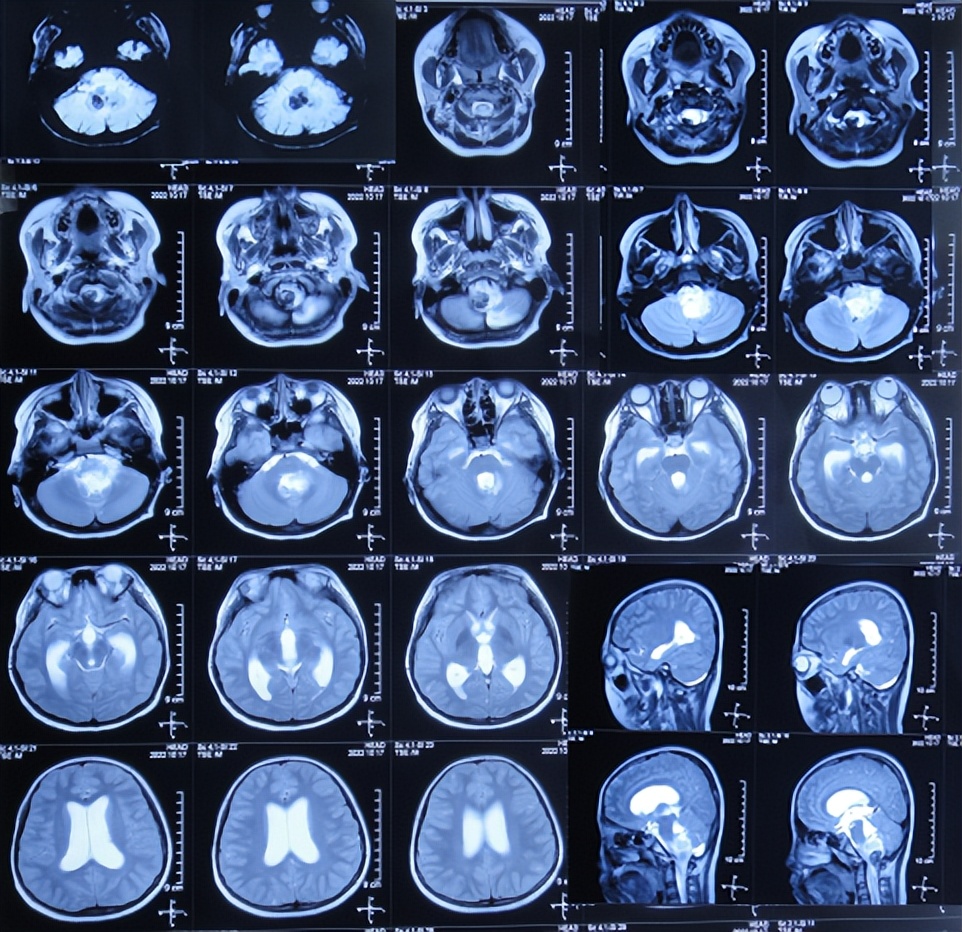

患儿于2022年10月10日,无诱因出现颈部疼痛,伴恶心呕吐、精神差,当时意识清楚,没有就诊,5天后即2022年10月16日,凌晨再次出现恶心呕吐多次,精神差,变得嗜睡,能被叫醒,就诊于山西省大同市浑源县某医院,查颅脑CT( 图-1 )示“小脑出血”,给予止血对症治疗。

图-1: 2022年10月16日颅脑CT上午11点